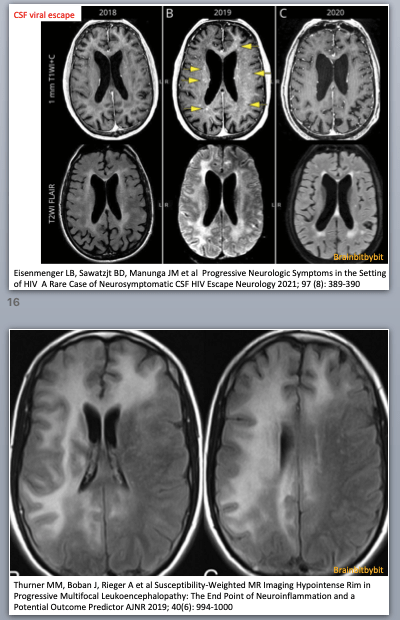

Pattern recognition on MRI is enabled by knowledge of the different cell types: E.g. in microglial pathology (HIV encephalopathy and leukodystrophies) the subcortical white matter is spared because the U fibers have low myelin turnover.

If the myelination pattern does not concur with the calender age, there can be hypomyelination or dysmyelination, meaning that not enough myelin is formed. Leukodystrophy is a term used for rare disorders involving (mainly) white matter with an underlying genetic, metabolic cause and symmetrical involvement as a key MRI finding(47-52). In demyelinating disorders there is destruction of previously formed myelin. The most known and prevalent demyelinating disease is not a leukodystrophy but an inflammatory one: multiple sclerosis, with a specific pattern of (non-symmetrical) white matter abnormalities on MRI located periventricular, in the corpus callosum, juxtacortical and infratentorial (39).